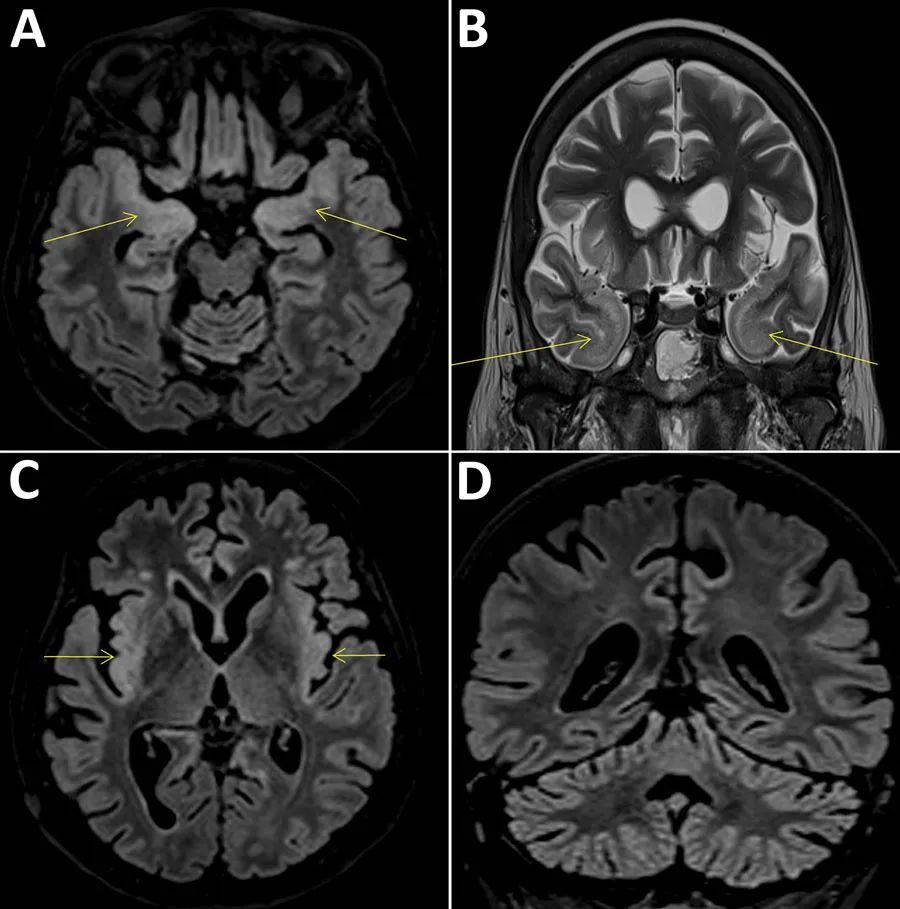

在接受了简单的治疗之后,妇人的病情明显好转,没过几天就回家养病了。可奇怪的是,一个月过后,这位妇人再次发起了高烧。当她再次被送入Pitié-Salpêtrière医院的病房时,医生惊讶的发现,这位妇人得了严重的脑炎。

入院之后,医生不仅为她做了微生物检测,还做了脑活检,但却找不到任何能够导致脑炎发作的原因。 6个月后,这位妇人最终因为严重的脑炎去世,只给医院里的医生留下了一地的谜团。在这位病患死后,Pitié-Salpêtrière的医生将妇人的脑组织送到了对传染病更有研究的Henri Mondor医院,希望他们能够找出答案。